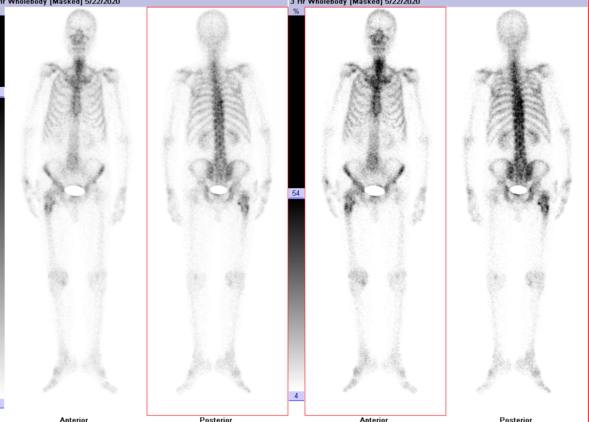

全身扫描ECT图